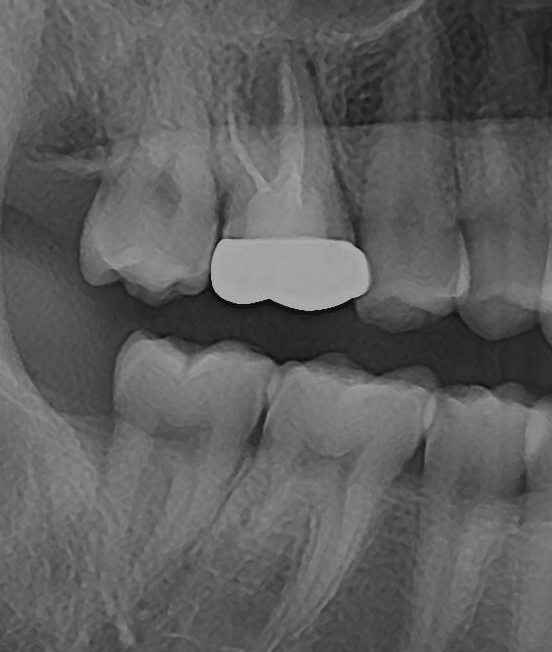

2. 두 치과 모두 뿌리염증이 있다고만 하고 어느 정도인지는 구체적으로 설명을 안 해줬습니다. 사진 상으로 어떤 정도인지 궁금합니다(비교용으로 그간 찍었던 사진을 같이 첨부했습니다) 최근 파노라마를 보면 오른쪽 신경 옆쪽으로 약간 검은 음영이 있는데 이게 뿌리 염증일까요?

3. 파노라마나 CT를 보면 16번 치아 뿌리쪽과 부비동쪽 둥그런 구조물 사이가 검게 음영이 생겨 있는데 이게 구조물의 영구적 손상이 있는 걸까요? 아니면 치료 후에 다시 회복되는 걸까요?

2017년 파노라마

2019년 파노라마

2022년 7월 파노라마

23년 6월 파노라마, 치근단

-사진상으로 보면 재신경치료를 하시는것보다는 발치를 해야될 가능성이 높아 보이네요.

-저부위는 염증때문에 펴가 녹아서 나타나는 부분으로 발치후 어느정도 기다리면 뼈가 차긴찹니다.